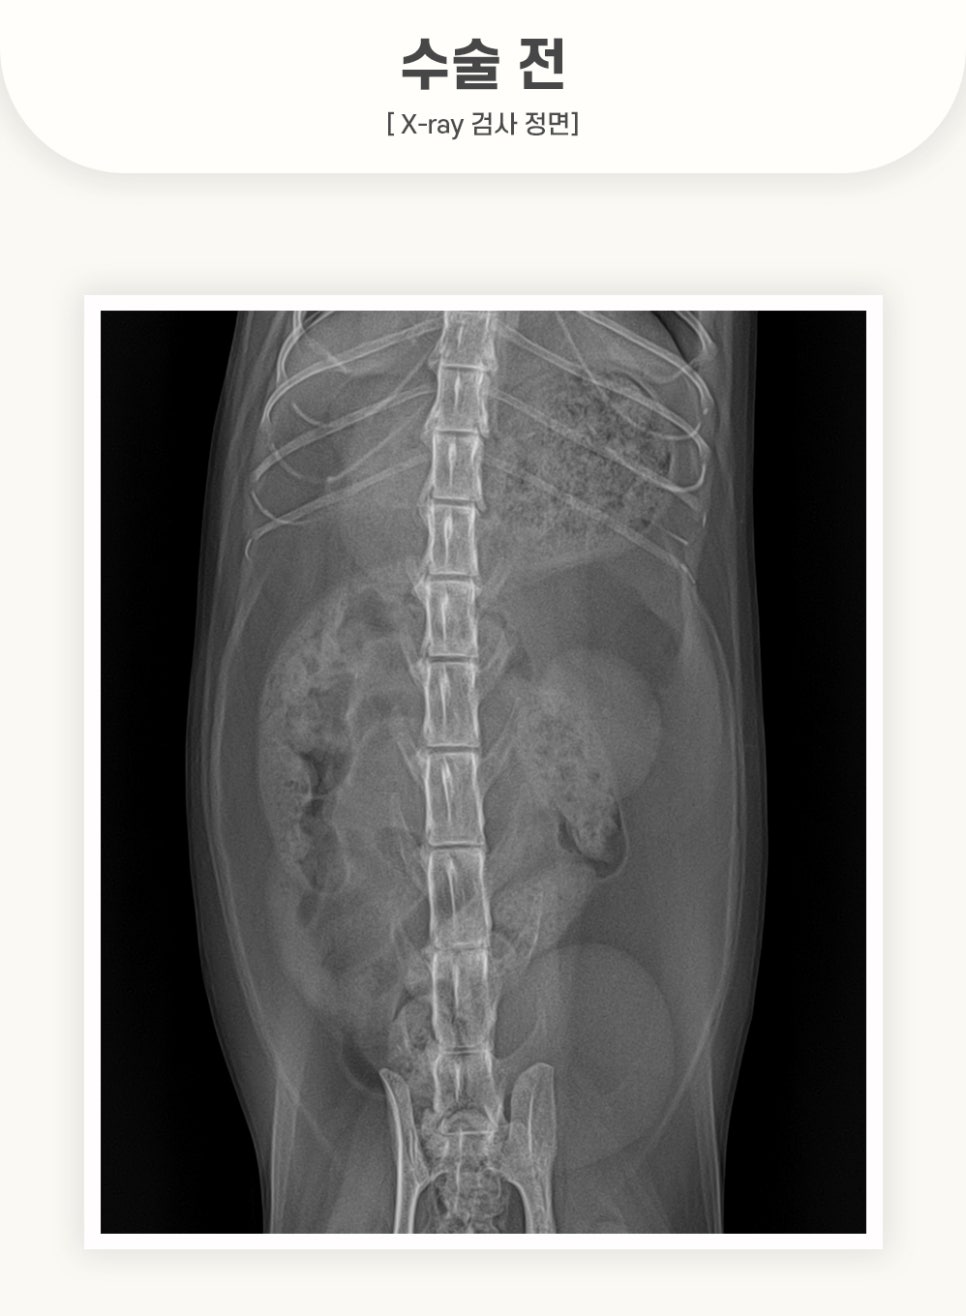

[수술 전 X-ray 검사]

예* 환자의 방사선 검사 시, 고양이 위 이물질이 크게 의심되는 상황이었습니다.

경기동물의료원에서는 이물질이 장내로 넘어가게 되면, 선형이물로 작용할 위험성이 있다고 판단하여 고양이 내시경 수술을 진행하게 되었습니다.